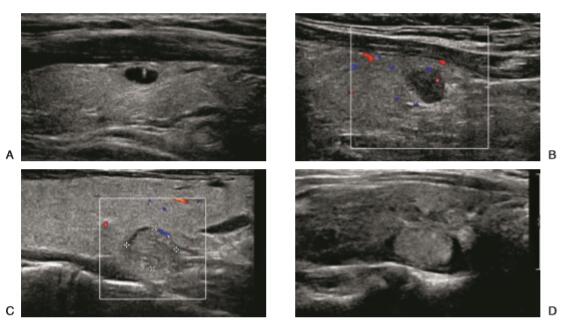

图文理清:甲状腺结节的超声诊断

超声引导下三种介入方法治疗甲状腺囊性结节效

甲状腺胶质潴留结节,一般以青少年人群多见,女生多于男性,B超表现为双侧多发甲状腺囊性结节,结节一般小于10mm,结节内可见典型的 彗星尾 征象,属高碘性甲状腺肿常见的特